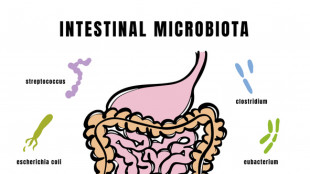

Con il latte materno si trasferiscono i batteri 'buoni' nel microbiota dei neonati

Lo studio sull'impatto dell'alimentazione delle madri, osservata continuità biologica

Il microbiota intestinale si compone già nei primi mesi di vita

Studio Campus Bio-medico-B.Gesù, da latte materno le prime tracce della salute futura